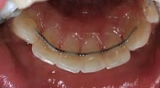

![]() |

| Unauffällig geklebte Drähte auf der Innenseite | Abnehmbare Geräte, Platten, häufig nur nachts getragen | Positioner. |